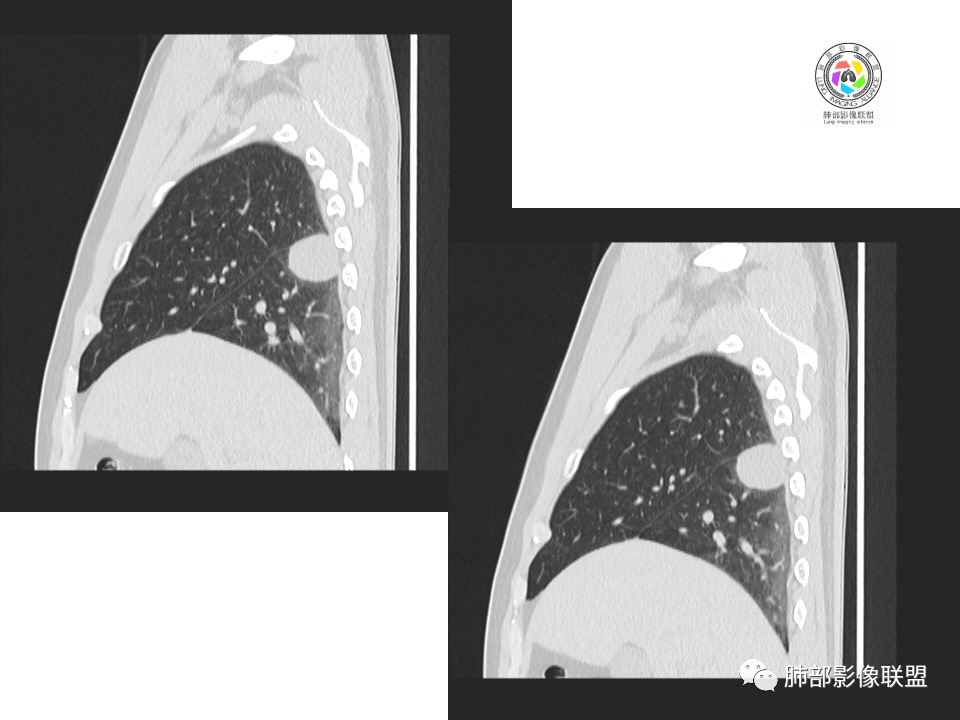

中年男性,20余年吸烟史,体检发现,右肺下叶胸膜下软组织肿块,边界清楚,边缘平直,有压迹,密度均匀,增强强化不明显,未见坏死区,考虑良性可能,炎性肉芽肿?。右肺下叶一小结节影,多个层面均有,考虑整体呈管状,走行与支气管相似,增强强化不明显,支气管来源可能,粘液栓?右肺中叶外周见斑点状、小结节状影,炎性病变?一元论,支气管来源病变,支气管囊肿?粘液栓?阻塞性炎症?长期吸烟史,鳞癌不除外。

2.右肺下叶背段胸膜下块影,边界清楚光整,上下极见磨玻璃晕,未见明显分叶毛刺和棘状突起,未见胸膜凹陷或胸壁侵入。密度均匀,轻度不均匀强化。未见支气管进入。

3.右肺中叶外侧段胸膜下散在小片影,磨玻璃密度为主,边界不清,支气管相关。符合炎性特征!

4.右肺下叶基底段支气管血管束旁小结节影,边界清楚,强化不明显。注意,这结节在“遥远的”基底段。

关于结节型隐球菌

1、普通人隐球菌感染的时相:初期的隐球菌感染周围有晕,晕从多变少,或包裹,或吸收,结节实性区可迅速变大。后期(慢性期)的隐球菌周围无明显晕征,边界较清楚。

2、有些模糊晕消失慢的原因:隐球菌对周围肺组织破坏相对不重,周围所供应的营养不多,增殖也不快,呈局部相安无事的状态。隐球菌消灭之后,肺泡间隔的炎症细胞及间质恢复更慢,所以经常能见到隐球菌外面隐约带细丝的模糊影。

3、卫星灶与“蘑菇兄弟”:诊断隐球菌时,建议找卫星灶,卫星灶可以在遥远的地方。可以是遥远地方的微小结节——“小蘑菇兄弟”。有些远处的卫星灶,通常是不规则饱满实性的,晕征不明显。隐球菌的卫星灶非常“隐”,但发现率高达60%多,诊断价值高。

4、卫星灶距离远的原因:隐球菌卫星灶常很远,推测:一次空气来源隐球菌感染进入双肺多处,部分定居繁殖;距离近的隐球菌“蘑菇兄弟”常常是二次感染。

5、周围毛刺纤维、边缘形态等:坏死包裹会使得结节变圆;结节多缺乏明显的分叶征,缺乏局部突出生长能力;如果出现分叶,是由多处肉芽肿中心形成。没有坏死的局限化,结节只是凑合在一起,常呈方形征;毛刺进入晕区(概念源自南边老师),毛刺较短、较软;周围的晕吸收后,会留下不规则边,外面常残留丝状条索;收缩力较弱,临近胸膜对胸膜牵拉不明显。

6、隐球菌的毛刺消失于晕区的解释:隐球菌结节周围有间质淋巴细胞增多,肉芽肿性炎延伸,以及纤维组织增生,形态并不规则,不是因为收缩力。

7、其他:隐球菌实性区相对腺癌更实,一旦实变里面就没空气,胸膜牵拉线(小叶间隔)拉的不太紧。